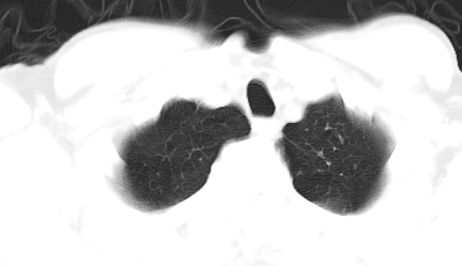

标题: CT10147:男、55岁,咯血10天,有结核病史。 [打印本页]

标题: CT10147:男、55岁,咯血10天,有结核病史。

双肺上叶结核

支持左肺中心性肺癌并纵隔及肺门淋巴结转移,左肺陈旧性结核。